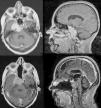

ResultsWe had fourteen patients (male/female 2:1), with a mean age of 49 years for chordoma and 32 for chondrosarcoma. The most common clinical presentation was diplopia in 78.5% of cases, followed by dysphagia in 28.6%. Histologically, 71.4% were chordomas and 28.6% were chondrosarcomas. In addition, invasion of at least two-thirds or more of the clivus was found in 81% of the cases; in 57.1% there was intradural invasion, and in 35.7% invasion of the sella turcica. In 42.8% of cases, the degree of resection was total and in 21.5% subtotal. The most common complication was CSF fistula, occurring in 28.6% of the cases, with only one case requiring surgery to repair it. Adjuvant treatment with Proton Beam was performed in 35.7% of cases and with conventional radiotherapy in 21.5%. Mean follow-up was 53.5 months and tumour recurrence or progression was found in 21.5% of the cases, two of which had not received adjuvant treatment. There were no deaths.

ConclusionThe extended endoscopic endonasal approach (EEEA) performed by an experienced team is a good alternative for the management of these lesions. Intradural invasion may be related to an increased risk of complications and worse clinical presentation, in addition to a lower rate of total resection.